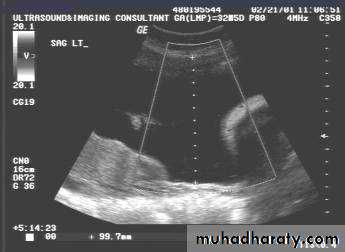

UUUUUUs of pelvic organs

Ovaries